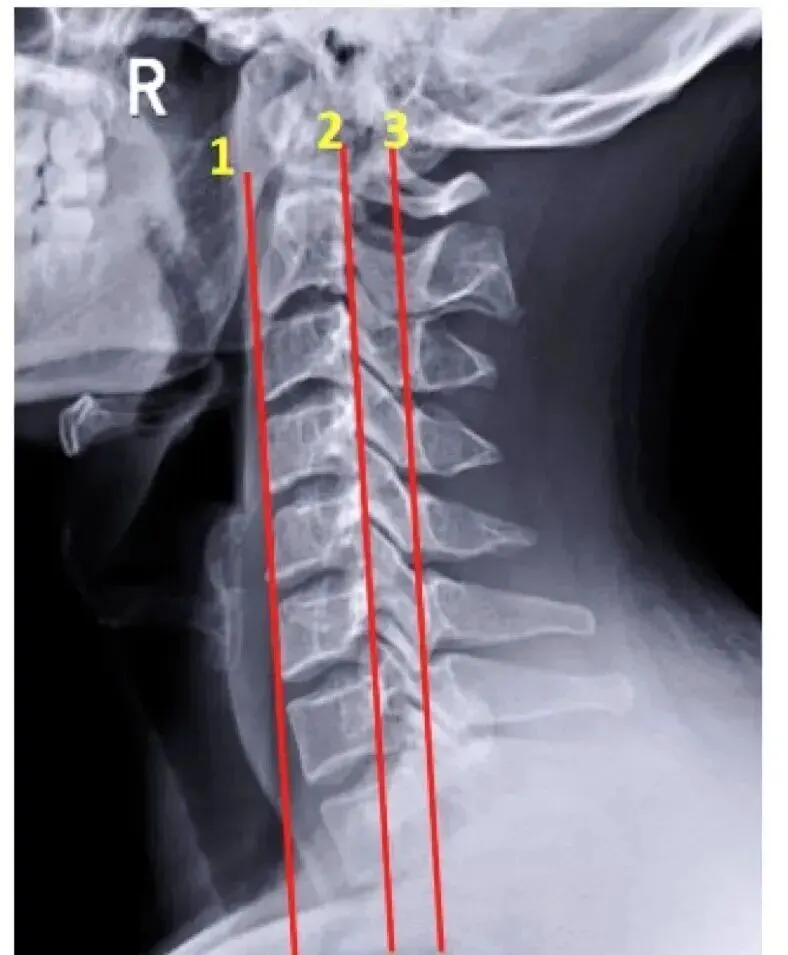

(二)侧位片观察要点

5.关节突关节:呈叠瓦状排列,关节间隙均匀